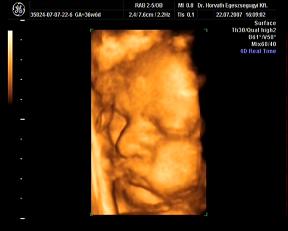

ma megvolt a -ha minden igaz- utolsó ultrahang. Nagyon jó volt, kisit furcsa érzés, hogy Ákossal már nem megyünk ilyenre...de nemsokára gyönyörködhetek benne állandóan 4D-ben-hanggal:D:D:D

Nagyon jól van, hála Istennek, csinált adoki flowmetriát is-az is rendben teljesen. A súlya 2870 gramm-ideális, a méretei a korának megfelelőek. A doki azt mondta, úy készüljek, hogy maximum két hétvégém van még az Urammal kettesben:D:D:D Nagyon várom már!!

Rakok náhény képet:

édes kis grimaszai vannak, nem? :oops: